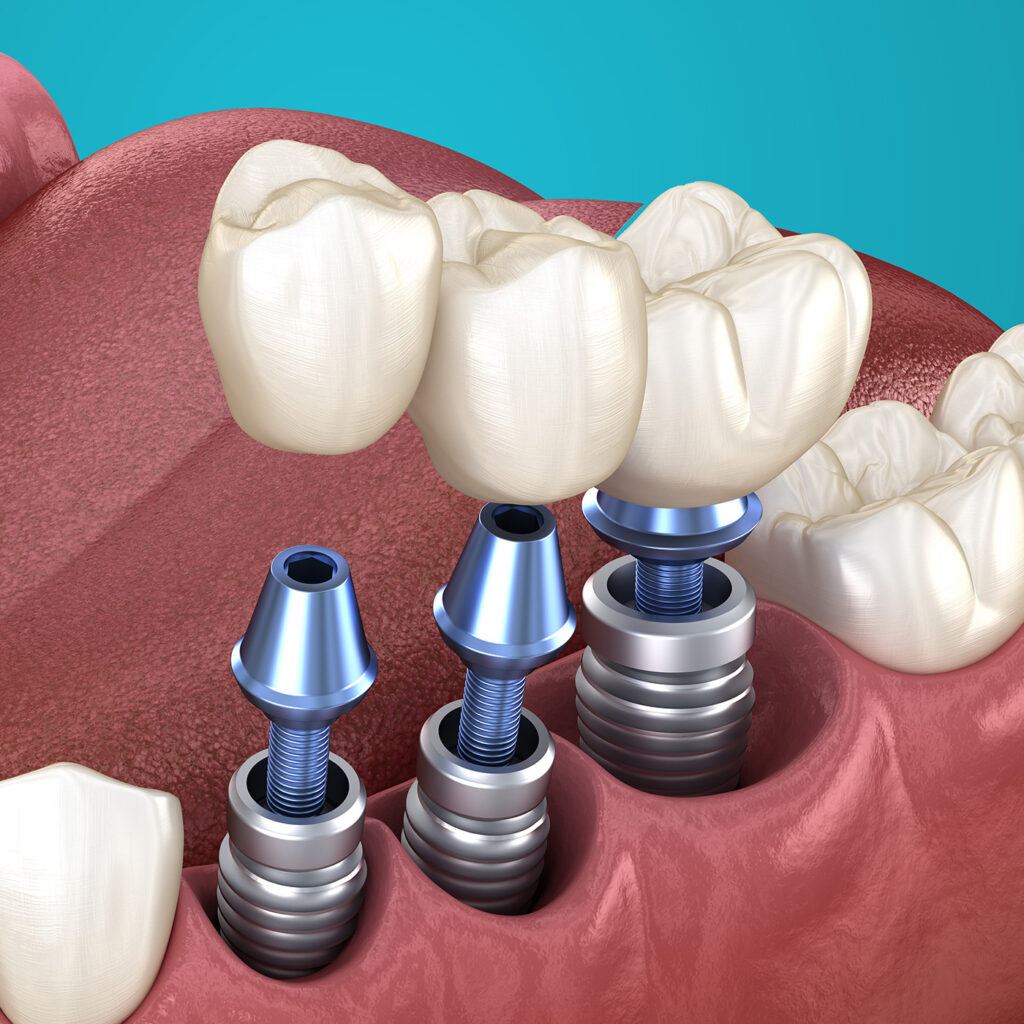

What is a Dental Implant?

People often think of the Implant as the complete package, but the Implant is the most important foundation. An Implant itself is not much of a presence in the mouth, and requires a CROWN that is seen, felt, and functioned with.

Careful planning, and placement is crucial for a great outcome.